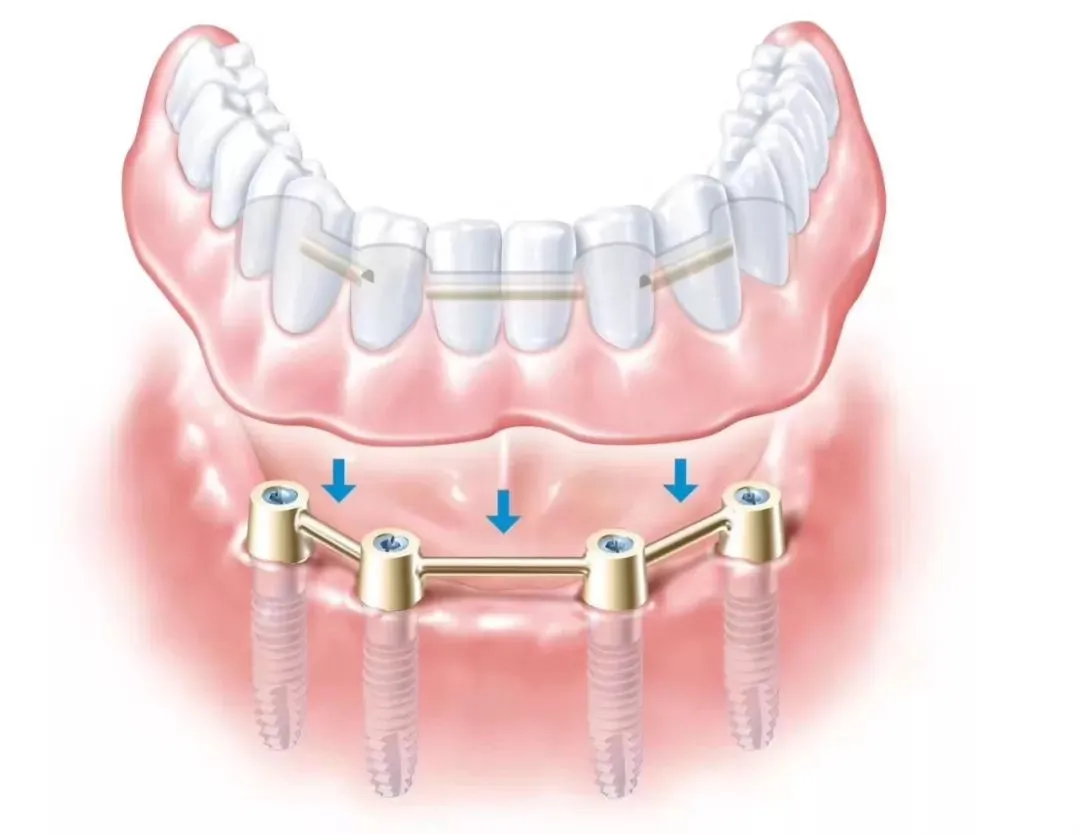

种植牙是医学界公认的理想修复方式,被誉为“人类的第三副牙”。相比活动假牙不舒服、难清洗、容易引起口腔黏膜病变,种植牙更稳固耐用,舒适美观,咀嚼功能好,一次种植,终生受用。种植牙不仅是中老年人的专利,年轻人因意外、牙病等造成牙齿缺失,也能够通过种植牙进行修复治疗,重获美丽笑容。

(All-on-4 全口/半口种植)